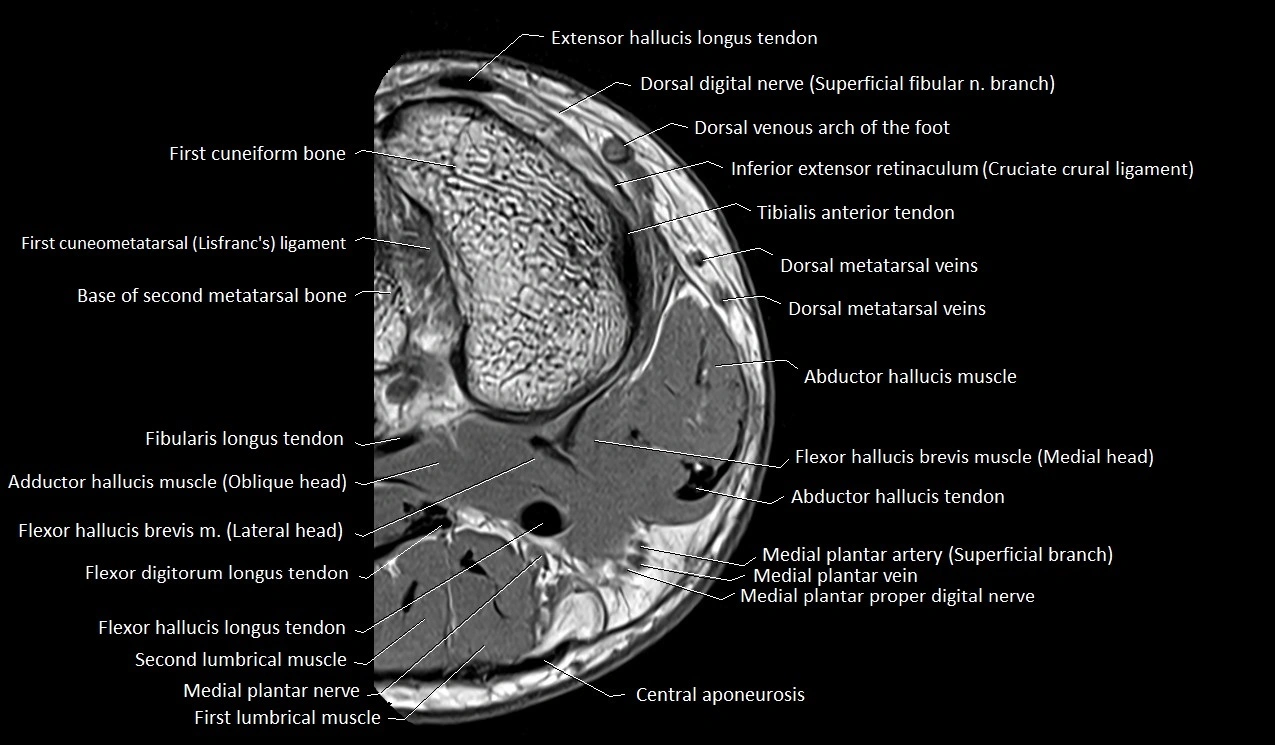

MRI image

image